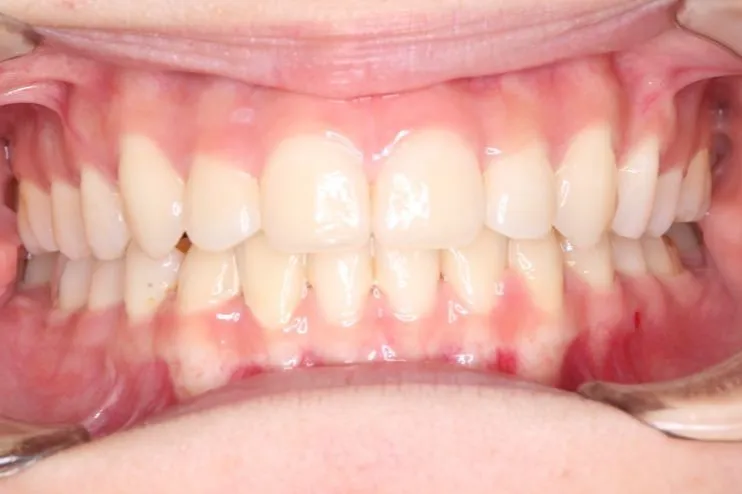

• 治療終了後

治療終了後

叢生は解消し、口元が大幅に引っ込み、下顎面高も縮小しました。

主訴が改善され、ご満足頂きました。